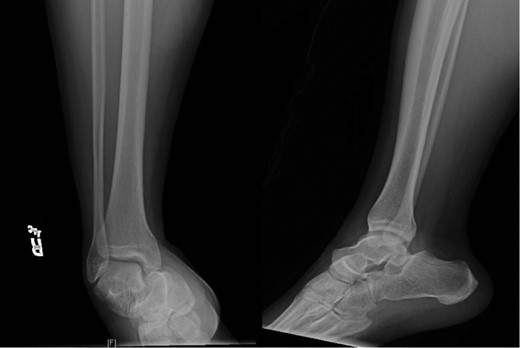

This patient is a 30-year-old male who presented to our emergency room following a head-on motor vehicle accident as a restrained driver. He described pain in his right ankle immediately after the accident and was taken to the emergency department as a trauma alert. ATLS protocol was instituted but no other injuries were identified. The patient’s right ankle was grossly deformed and locked in supination but skin was intact (Fig. 1). The right lower extremity was neurovascularly intact. Initial X-rays (Fig. 2) of the right ankle demonstrated a medial subtalar dislocation without associated fractures. In the emergency department, closed reduction was attempted under conscious sedation but was unsuccessful. Therefore, risks, benefits and alternatives were discussed and the patient elected to proceed with urgent closed vs open reduction of the right subtalar joint and any other indicated procedures.